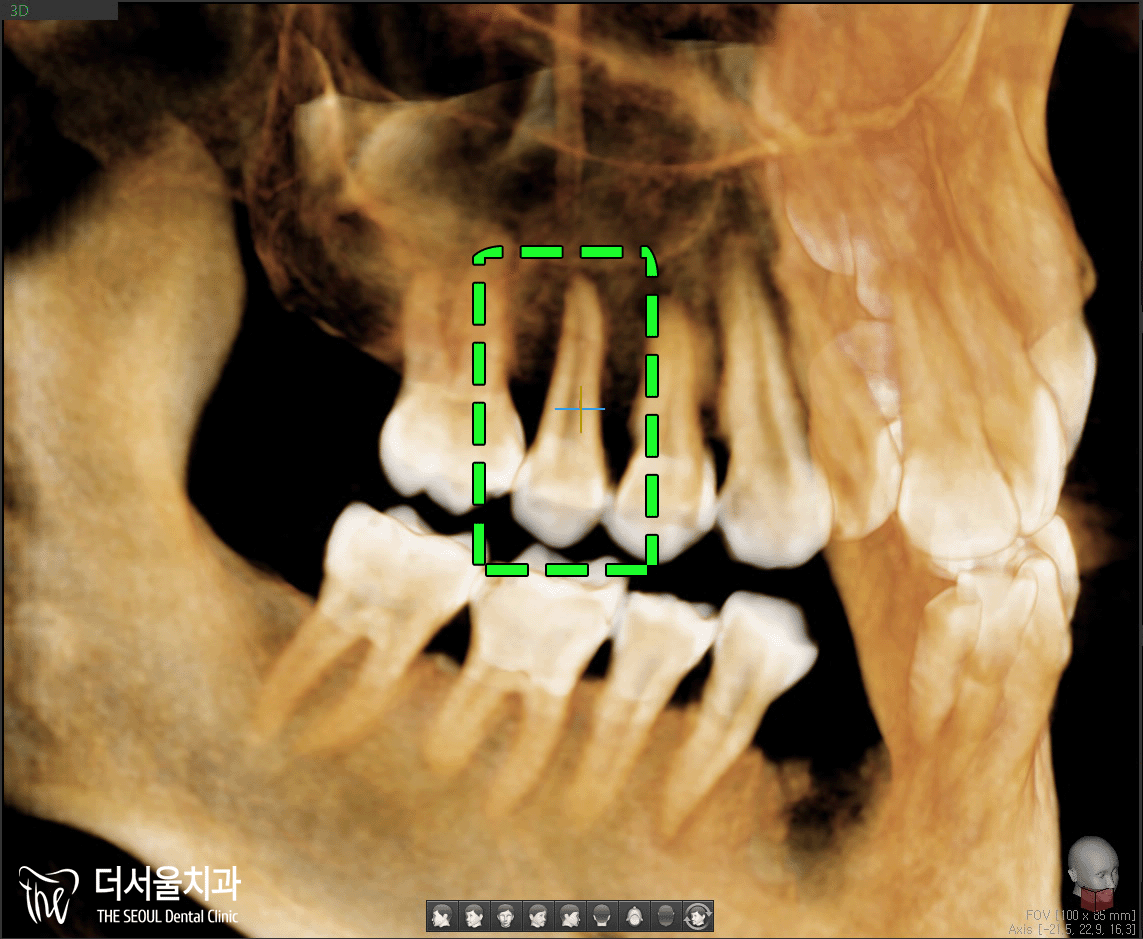

3D CT를 통해 확실히 체크해보겠습니다.

해당 치아입니다.

오른쪽에 단면을 보면,

수직으로 깊게 깨져있죠?

뿌리까지 파절되었기에

이를 살릴 수 없었습니다.

어떤 방향으로 봐도

뿌리까지 깊게 그어져있는 선을 볼 수 있습니다.

결국 발치 후 임플란트 식립을 하기로 했는데요.